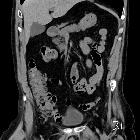

Schenkelhernie mit Appendix vermiformis

Gangränöse

Appendicitis in Schenkelhernie (De Garengeot Hernie): Zahlreiche Gaseinschlüsse im Bruchsack. Oben links axial, unten links sagittal, rechts 2 Schichten koronar.

Schenkelhernie

mit in diese hineinziehende Appendizitis: De-Garengeot-Hernie. Computertomographie axial und coronar. Das entsprechende Pendant in einer Leistenhernie heißt Amyand-Hernie.